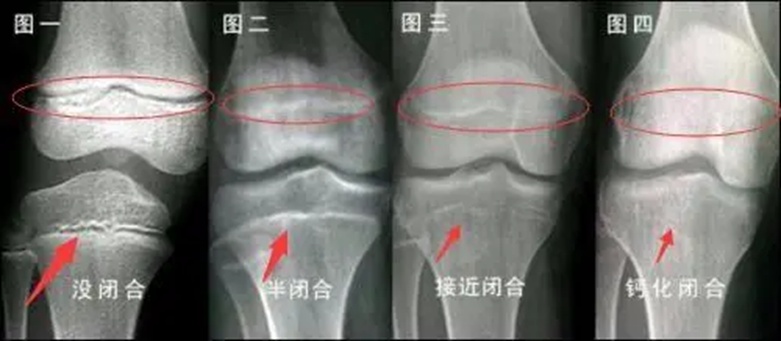

骨骺线,即生长板,位于骨骺与骨骼干骺端之间。一旦生长板消失,也就是骨骺线闭合,身高便会停止增长。判断孩子身高增长潜力以及是否停止生长,最科学的依据是骨龄。

通常情况下,女孩的骨龄在 13 岁左右基本趋于闭合,男孩则在 16 岁左右。不过,即便手腕部的生长板闭合,脊柱或膝盖等部位或许仍存在少许生长余地,但极为有限。